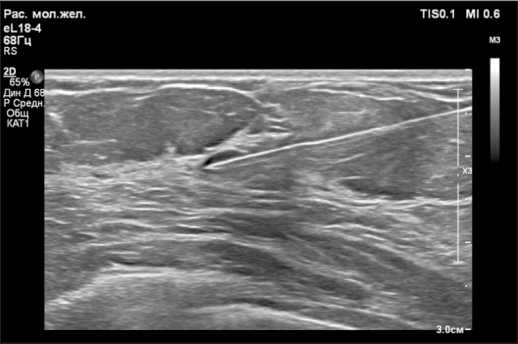

При УЗИ молочных желез через 4 мес после первичного обследования: BI-RADS-4а справа, BI-RADS-2 слева. Эхо-картина фиброзно-кистозных изменений молочных желез с преобладанием железистой ткани. В правой молочной железе на 12 часах условного циферблата определяется гипоэхогенное образование овальной формы с четким ровным контуром, размерами 1,0×0,4 см, периферическим кровотоком, предположительно фиброаденома, отмечен некоторый рост в динамике от марта 2024 г., выполнена трепан-биопсия. Аксиллярные лимфатические узлы с сохраненной дифференцировкой (рис. 1, 2).

Рис. 1. УЗ-картина гипоэхогенного образования на границе верхних квадрантов правой молочной железы.

Примечание: рисунок выполнен авторами

Fig. 1. Ultrasound image of hypoechoic lesion at the border of the upper quadrants of the right breast. Note: created by the authors

Рис. 2. Допплеровское картирование: демонстрация периферического кровотока.

Fig. 2. Doppler mapping: demonstration of peripheral blood flow. Note: created by the authors

Рис. 5. УЗ-картина локализационной иглы в проекции опухоли. Примечание: рисунок выполнен авторами

Fig. 5. Ultrasound image of the needle’s location in the projection of the tumor. Note: created by the authors